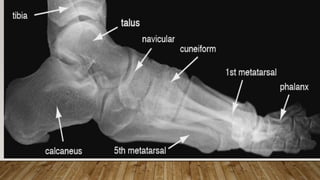

This document discusses radiology and the use of x-rays. It begins with an introduction to radiology and x-rays, noting their importance as the "father of medical investigations." It then discusses anatomy as seen on radiographs and whether x-rays are enough. The document goes on to compare gross views to radiological views, noting what each can and cannot show. It highlights important figures in the development of radiology, from x-rays to CT, MRI, and ultrasound. Specific anatomical structures visible on upper and lower limb x-rays are listed. The document concludes by discussing how pathologies appear on x-rays and the importance of clinical history and knowledge when interpreting radiological images.